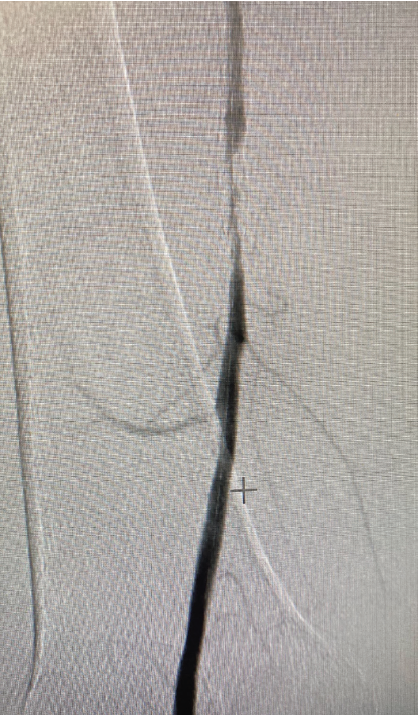

An arterial Doppler and subsequent diagnostic peripheral angiogram showed severe in-stent restenosis of the Supera stent in the right superficial femoral artery (SFA) (Figure 1). The patient was evaluated for surgical femoral popliteal artery bypass surgery versus percutaneous transmural arterial bypass (PTAB) with the DETOUR System (Endologix) (Figure 2). Due to frailty, poor pulmonary function tests, and patient preference for a minimally invasive approach, she was further evaluated for the PTAB procedure.

The SFA lesion was approximately 80 mm post atherectomy. The femoral vein was measured by Doppler and found to be >10 mm in diameter. The proximal SFA and popliteal artery were deemed acceptable in diameter (>6 mm) for a transmural bypass.